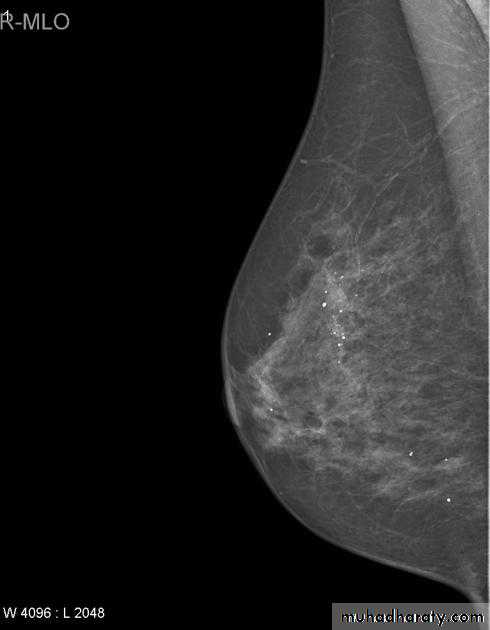

The mediolateral oblique (MLO) view is one of standard mammographic views. It is the most important projection as it allows to depict most breast tissue.